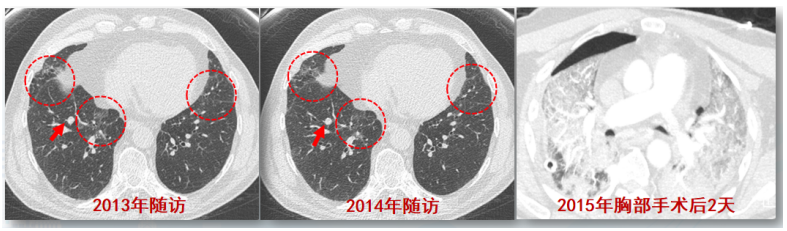

(1)感染性疾病:病毒性?细菌性?真菌?非典型病原体?吸入性肺炎?(2)非感染性疾病:心衰?急性肺栓塞?自身免疫性疾病?麻醉/手术相关肺损伤?急性间质性肺炎?回顾分析患者入院时胸部CT: 双肺靠近外周近胸膜处有轻微细小间质样改变(图4)。诊断:急性间质性肺炎;Ⅰ型呼吸衰竭;左肺下叶部分切除术后;高血压病。ECMO支持;呼吸机支持;甲泼尼松80 mg q12h,尼达尼布;镇静镇痛;抗感染;营养支持。ECMO第6天, 术后第18天, 肺部病变进一步加重(图5)。血气分析: pH 7.543, PaO2 154 mmHg, PaCO2 33.2 mmHg(ECMO, FiO2 100%, MV FiO2 60%)。术后第26天复查胸部CT未见改善。患者最终死亡。笔者团队也曾接诊过一例早期肺癌患者,2013年和2014年随访肺部结节均无明显变化。2015年胸部手术后2天,两肺变白(图6)。当时医生警惕性非常高,立刻行胸部CT检查并予相应治疗,患者最终存活。2022年RadioGraphics 杂志报道一例85岁女性腺癌患者奥希替尼治疗5个月后。图7-A和B为治疗前胸部CT图像,可见右肺中叶有肿块(A中箭头)。胸膜下区域磨玻璃改变和网状结构(箭头)提示存在间质性肺异常(Interstitial Lung Abnormalities,ILA)。治疗5个月后的轴位CT图像显示肿块(C中白色箭头)、弥漫性磨玻璃改变和合并症(黑色箭头)。图源:Radiographics, 2022, 42(7):1925-1939.另一例66岁右上肺鳞癌患者,术前CT显示肿块(图8-A中箭头)位于肺右上叶。轻度磨玻璃改变(箭头),提示ILA,见于胸膜下区域。图8-C和D为术后CT,显示弥漫性磨玻璃样改变和实变(箭头),牵引性支气管扩张症(图8-C中箭头),也可见胸腔积液(图8-D中箭头)。图源:Radiographics, 2022, 42(7):1925-1939.